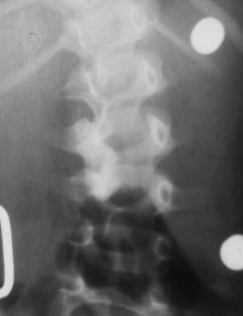

Es menos frecuente que en la población adulta, un 2% de la población pediátrica sufrirá de un disco herniado (21). Usualmente va a estar acompañado de un historial familiar positiva o de traumatismo. El paciente refiere dolor que se irradia hasta las piernas y que aumenta con actividades tan simples como estornudar, estar sentado o parado. El examen físico mostrará un paciente inclinado hacia el frente, con limitación de movimiento de la columna vertebral y dolor al levantar las piernas. El examen neurológico reflejará la disminución de algún reflejo, debilidad o adormecimiento aunque es menos frecuente este hallazgo en los niños que en los adultos (22). La radiografía puede mostrar una escoliosis reactiva al dolor o una disminución del espacio intervertebral, pero el mejor estudio es la RM (Figura 1). El tratamiento inicial será modificar las actividades, procurar descanso y medicación analgésica, relajantes musculares, infiltraciones epidurales y terapia física. Si no hay una respuesta adecuada al manejo conservador o hay alteración neurológica, estará indicada la remoción quirúrgica del disco herniado (22).